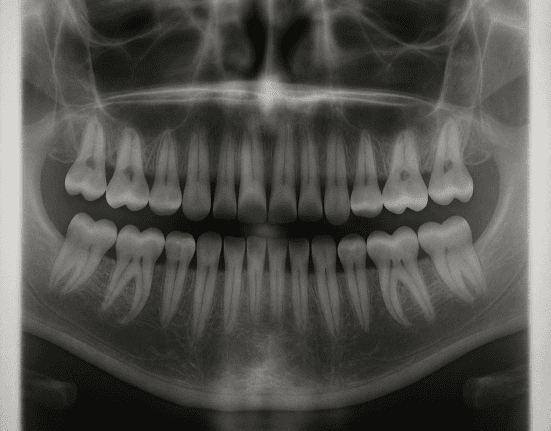

Photo credit: Image of dental x-ray AI generated.